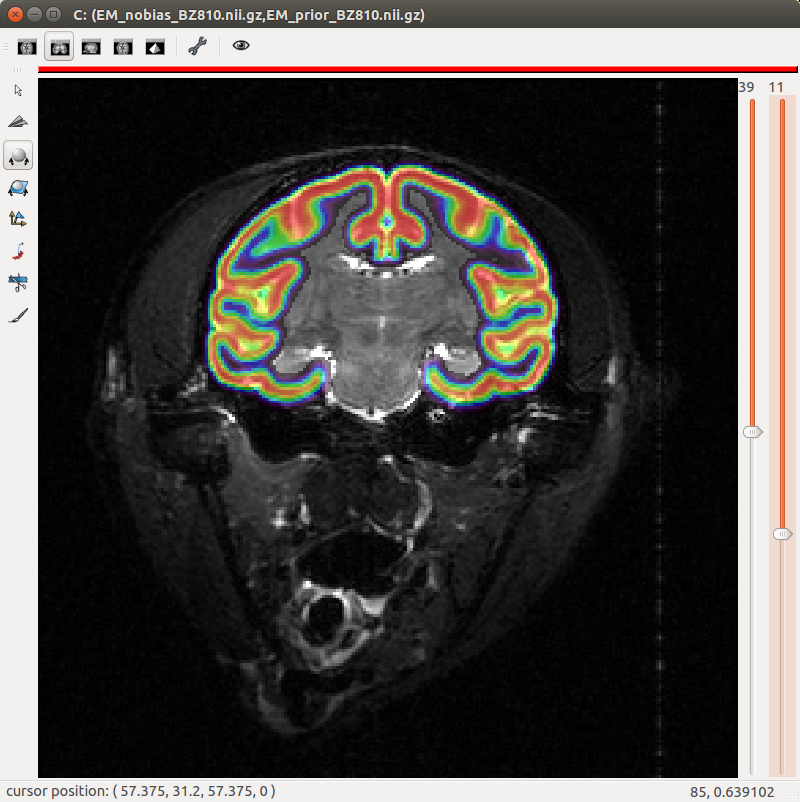

Figure 4. "Eye" visualization of the 4-class mixture and the full mixture results.